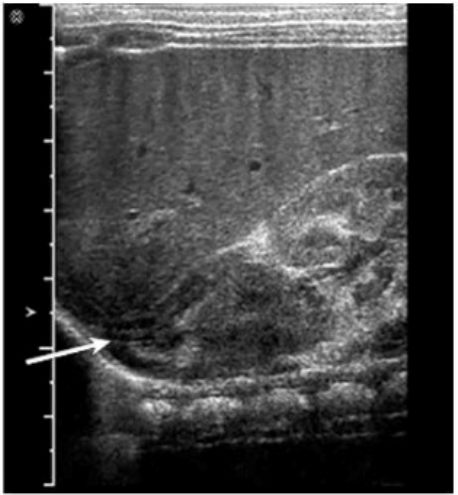

Which structure is indicated by the arrow in this image?

Answer : D

The structure indicated by the arrow in the ultrasound image is the adrenal gland. On ultrasound, the adrenal gland in neonates and infants is relatively large and has a distinctive ''Y'' or ''V'' shape in the transverse view. It is located superior and slightly medial to the upper pole of the kidney.

In this image, the arrow is pointing to a hypoechoic, curved structure with a thin echogenic central stripe, representing the fetal adrenal gland. This echogenic stripe corresponds to the adrenal medulla, while the surrounding hypoechoic area represents the cortex.

The adrenal glands are located in the retroperitoneum, superior to the kidneys, and appear prominent on ultrasound in neonates.

In transverse view, the right adrenal gland is anterior to the crus of the diaphragm and posterior to the inferior vena cava (IVC).